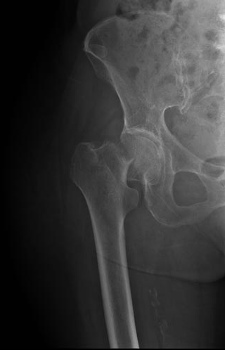

Example X-Ray Images

Femoral Neck Fracture